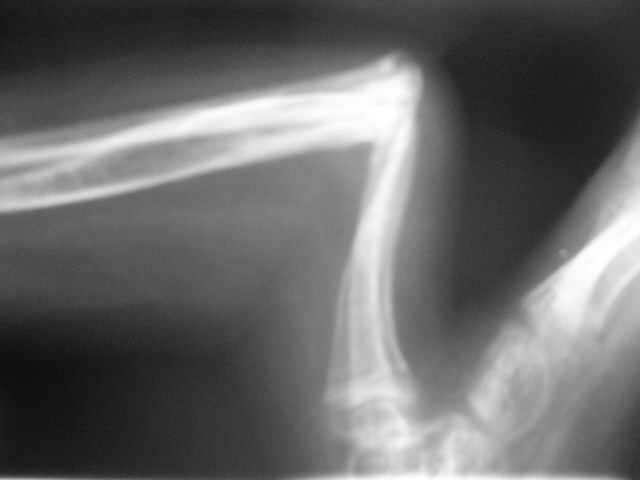

Уважаемые коллеги,Госпитализировали ребенка 4 лет с врожденной деформацией голени.

Нога опороспособна, безболезненна, выраженная хромота за счет укорочения.Признателен за рекомендации и высказанные мнения.Евгений И Чекашкин

диспластического типа с полной окклюзией к.м. канала.